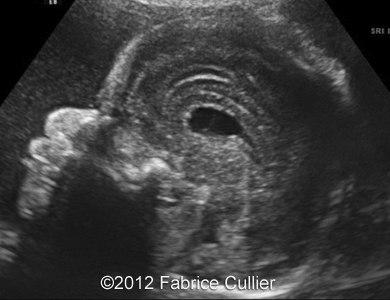

Images 1, 2: A transversal plane of the skull, too round (Brachycephaly).

1A

1B